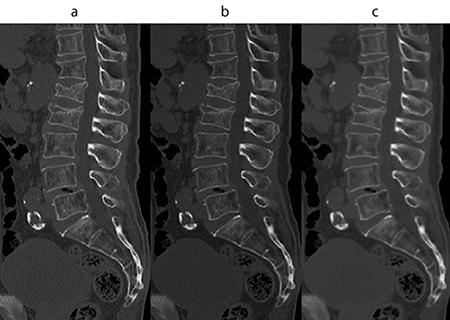

図6 腰椎圧迫骨折症例のMPR画像

a:骨用関数

b:標準関数フィルタ適用(ガウスエッジ強調2Level=3)

c:標準関数